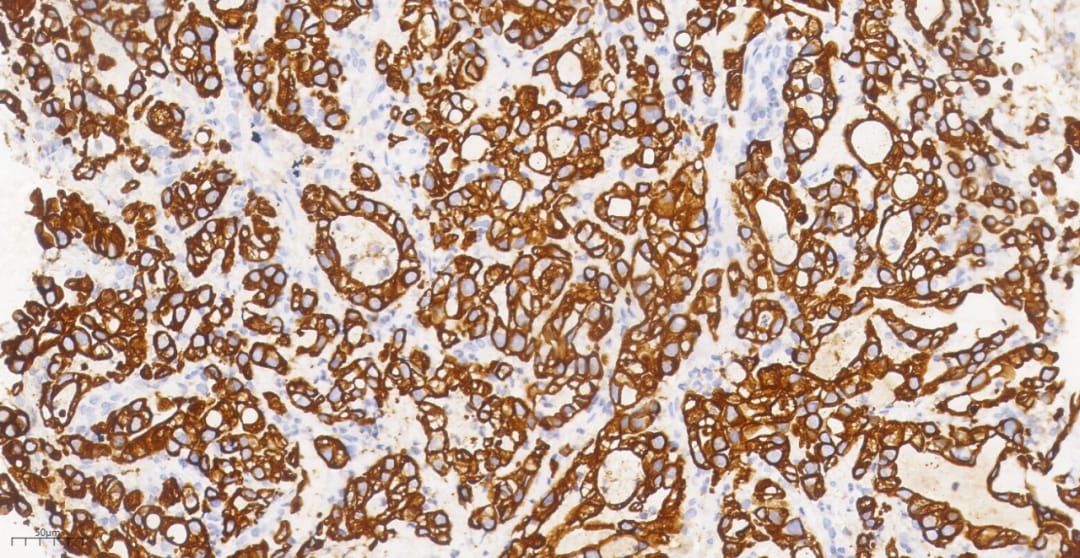

然而,要最终确诊,还需要进行一项关键的检测——免疫组化。这项技术就像是给细胞“染色”,通过观察特定蛋白质的表达情况来判断肿瘤的类型。结果显示,该患者的肿瘤细胞中,一种名为BRG1的蛋白质完全缺失(阴性表达)。BRG1蛋白是由SMARCA4基因编码的,它的缺失是诊断SMARCA4缺失性肿瘤的关键证据。

图7 免疫组化显示肿瘤细胞CK7阳性

图8 关键证据:肿瘤细胞BRG1表达缺失

综合所有检查结果,最终的病理诊断为:(左肺上叶开口)低分化腺癌,符合SMARCA4缺失性腺癌。这个诊断揭示了患者所患疾病的罕见性和侵袭性。